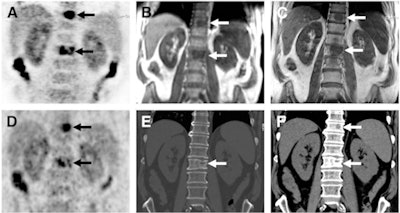

Images of bone metastases (arrows) in a 69-year-old man presenting for staging of oropharyngeal cancer: PET/MRI with coronal PET (A), coronal T1-weighted Dixon MRI sequence (B), and coronal T1-weighted TSE MR sequence (C). PET/CT scan includes coronal PET (D) and coronal bone (E) and soft-tissue CT (F). Two metastases in spine show intense uptake in both PET datasets (A and D). Replacement of bone marrow is seen in both T1-weighted Dixon MRI sequence (B) and T1-weighted TSE MR sequence (C), with better lesion delineation in TSE than in VIBE Dixon because of higher in-plane resolution. Faint sclerosis is present as anatomic correlate of caudal metastases in both bone window (E) and soft-tissue window (F) on CT, whereas cranial metastasis is depicted only in soft-tissue image. Images courtesy of JNM.

Images of bone metastases (arrows) in a 69-year-old man presenting for staging of oropharyngeal cancer: PET/MRI with coronal PET (A), coronal T1-weighted Dixon MRI sequence (B), and coronal T1-weighted TSE MR sequence (C). PET/CT scan includes coronal PET (D) and coronal bone (E) and soft-tissue CT (F). Two metastases in spine show intense uptake in both PET datasets (A and D). Replacement of bone marrow is seen in both T1-weighted Dixon MRI sequence (B) and T1-weighted TSE MR sequence (C), with better lesion delineation in TSE than in VIBE Dixon because of higher in-plane resolution. Faint sclerosis is present as anatomic correlate of caudal metastases in both bone window (E) and soft-tissue window (F) on CT, whereas cranial metastasis is depicted only in soft-tissue image. Images courtesy of JNM.As for characterizing the lesions, the researchers found no significant differences between the three image sets. Of the 90 malignant lesions, 85 were correctly classified in set A, 84 in set B, and 86 in set C.